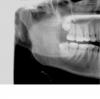

Рената Опубликовано 17 января, 2009 Поделиться Опубликовано 17 января, 2009 скорее всего была нарушена техника бондинга при постановке композитов,возможно препарировали без водяного охлаждения , плюс я думаю у вас вообще повышенная чувствительность эмали зубов ,меняйте врача, плюс обязательно начните принимать витамины- берокка с магнием и кальцием, либо отдельно магни-В6 и поменяйте пасту на сенсодин ф ,ну и коррекция прикуса нужнаДоминика!Здравствуйте!Я по поводу пациентки с болями в 46 и 45.Посмотрите,пожалуйста, 44 на апроксимально-дистальной поверхности разряжение в дентине или мне кажется?И в 45 апр.-мед.поверх-сть.Не отсюда ли боль от холодного ?А вот при накусывании?Всё-таки 46? Ссылка на комментарий

доминика Опубликовано 17 января, 2009 Поделиться Опубликовано 17 января, 2009 Доминика!Здравствуйте!Я по поводу пациентки с болями в 46 и 45.Посмотрите,пожалуйста, 44 на апроксимально-дистальной поверхности разряжение в дентине или мне кажется?И в 45 апр.-мед.поверх-сть.Не отсюда ли боль от холодного ?А вот при накусывании?Всё-таки 46?на 44 точно кариес, вы молодец ,глазастая Ссылка на комментарий

Улыбка счастья Опубликовано 17 января, 2009 Автор Поделиться Опубликовано 17 января, 2009 (изменено) Спасибо большое всем за ответы! Здесь уже много обсуждали про теплопроводность материалов ,про отрыв композита и полимеризационный стресс .У Вас все то наблюдается . Вряд ли вы все поймете ,но почитать можно .Большой Зеленый, не подскажите, в каком разделе об этом можно почитать?скорее всего была нарушена техника бондинга при постановке композитов,возможно препарировали без водяного охлаждения , плюс я думаю у вас вообще повышенная чувствительность эмали зубов ,меняйте врача, плюс обязательно начните принимать витамины- берокка с магнием и кальцием, либо отдельно магни-В6 и поменяйте пасту на сенсодин ф ,ну и коррекция прикуса нужнадоминика, cверлили с водой в 4 руки. Витамины, которые Вы посоветовали, куплю. Сейчас принимаю КальциД. Пасту Sensodyne зеленую использую и ROKS Венский десерт для чувствительных зубов. Доминика!Здравствуйте!Я по поводу пациентки с болями в 46 и 45.Посмотрите,пожалуйста, 44 на апроксимально-дистальной поверхности разряжение в дентине или мне кажется?И в 45 апр.-мед.поверх-сть.Не отсюда ли боль от холодного ?А вот при накусывании?Всё-таки 46?на 44 точно кариес, вы молодец ,глазастая Рената,доминика, это Вы про меня? Мне 45 лечили в там же. Там что-то тоже не так? А в 46 зуб нужно просто пломбу переустановить или все же удалить нерв, как Вы считаете, уважаемые врачи? P.S. Я первом посте снимок ДО лечения. Мне вылечили 45, 46 (сейчас больно накусывать +холодное), 47 и 15 (было больно накусывать + холодное). Изменено 17 января, 2009 пользователем Улыбка счастья Ссылка на комментарий

доминика Опубликовано 17 января, 2009 Поделиться Опубликовано 17 января, 2009 44 тоже надо лечить, там на контакте с 45 кариес Ссылка на комментарий